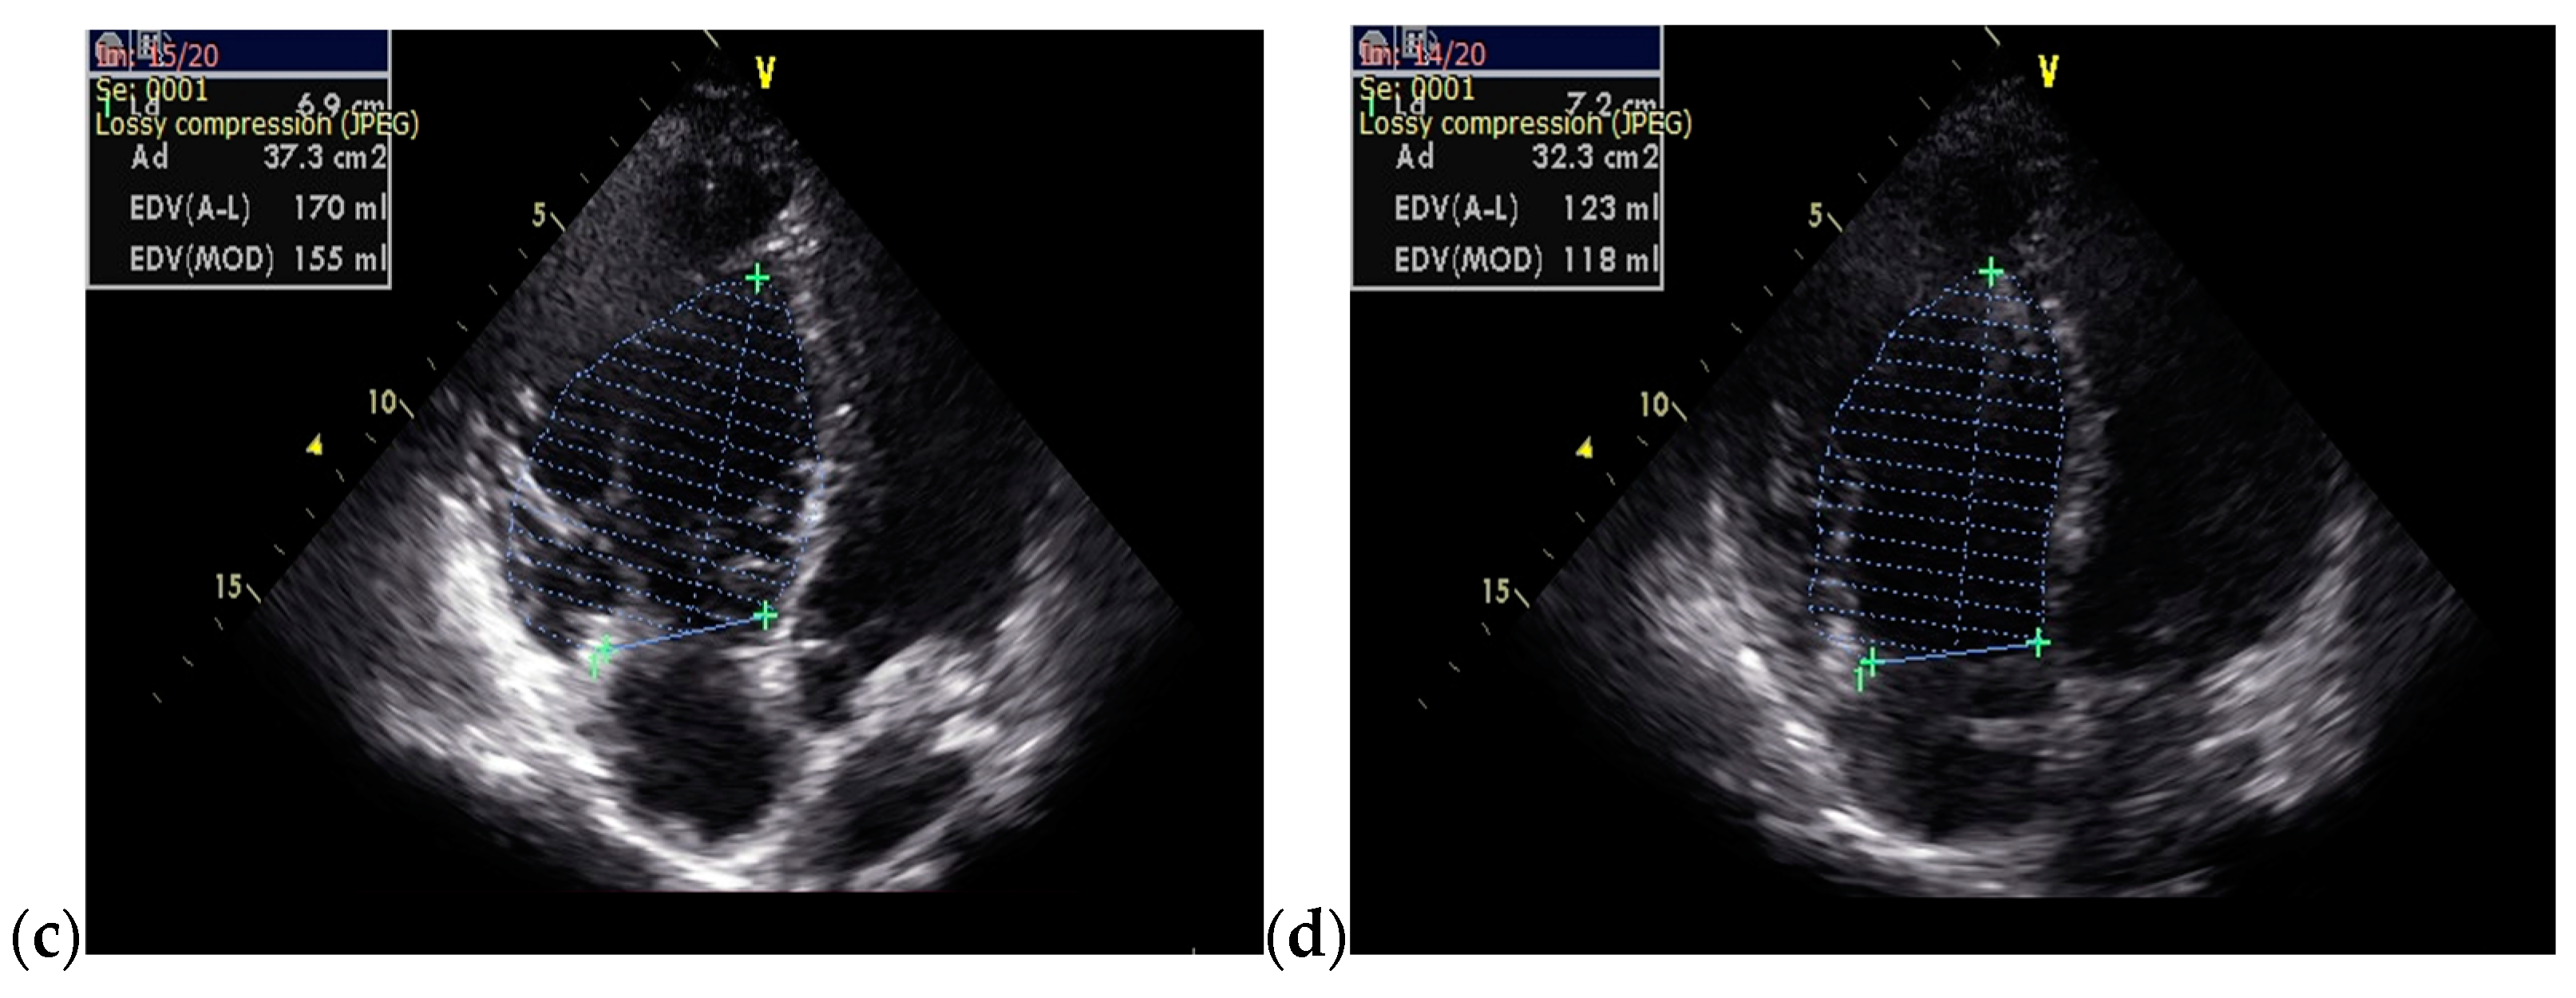

On admission, a TTE was performed and confirmed Ebstein’s anomaly. The main findings of the TTE were non-dilated left ventricle with an ejection fraction of 50% evaluated using Simpson’s method, dilated right chambers, atrialization of the RV, apical insertion of the septal cusp of the tricuspid valve, and mild functional tricuspid regurgitation (Figure 8).

Figure 8.

TTE on admission: (a) Apical 4-chamber view: dilated right cavities with a RV diameter of 7, 3 cm; (b) Apical 4-chamber view: total volume of the RV—252 mL; (c) Apical 4-chamber view: functional RV volume—170 mL; (d) Apical 4-chamber view: atrialized RV volume—123 mL; Abbreviations: TTE—transthoracic echocardiography; RV—right ventricle.